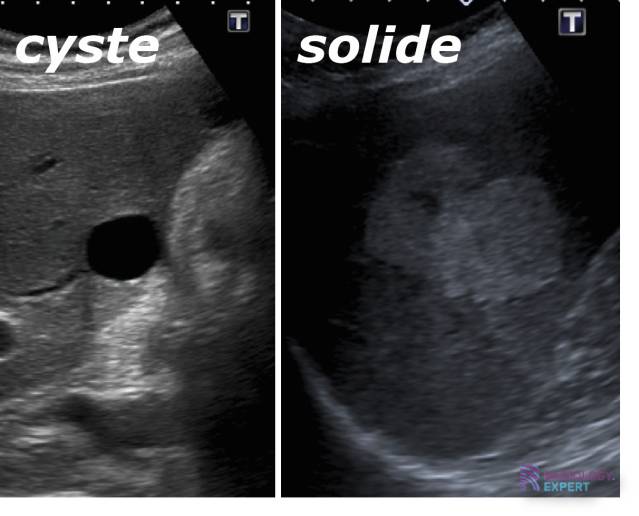

Het woord 'cyste' kan direct onrust oproepen. Het is belangrijk te beseffen dat het simpelweg een zakje gevuld met vocht is. In de context van de borst, kan een cyste aanvoelen als een knobbeltje, wat begrijpelijk is dat je je even zorgen maakt. Maar voordat de paniek toeslaat, laten we de kennis verwelkomen als een vriend, een gids die ons inzicht verschaft.